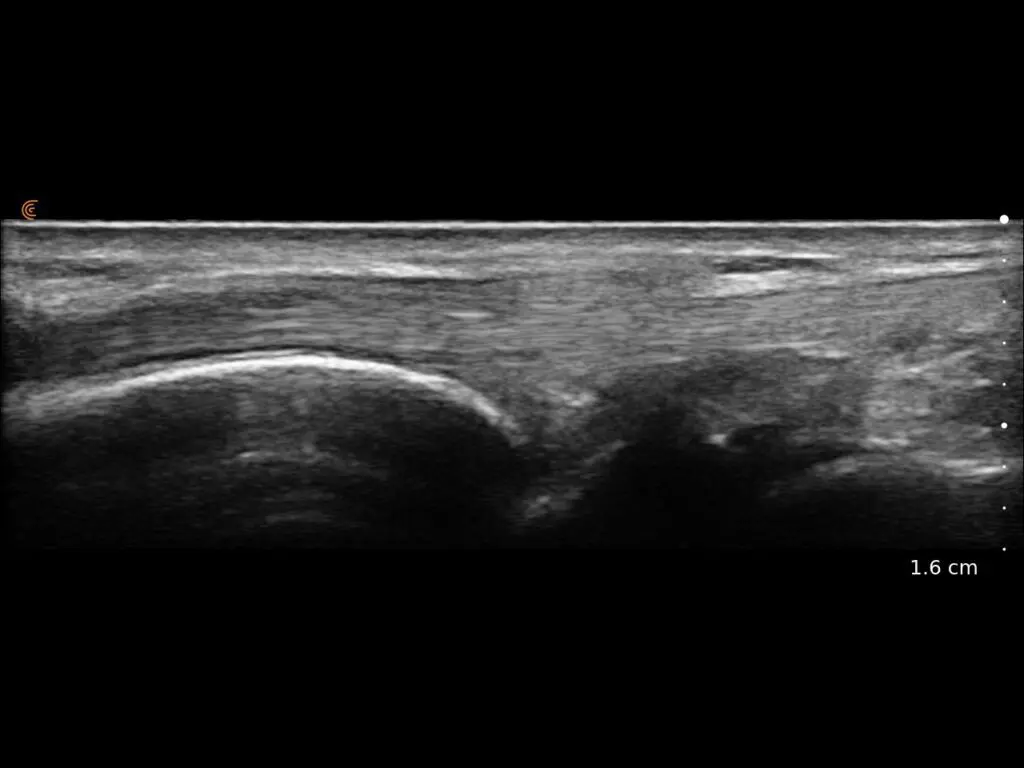

ProbeFix Dynamic is a new device that enables high-quality ultrasound measurements during dynamic exercise by keeping an ultrasound probe in place, allowing for muscle monitoring during intense movement and creating new research possibilities in muscle imaging.